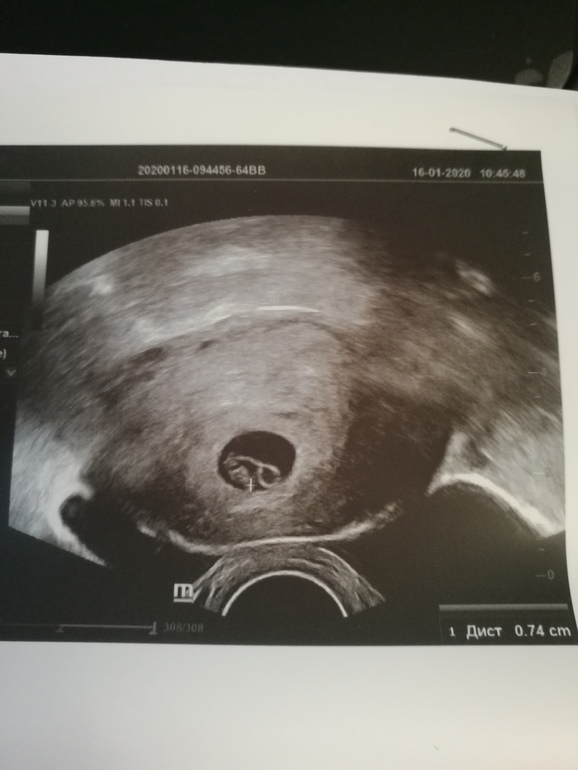

УЗИ 30 дпп

Анализы и процедуры. Помощь в расшифровке результатовДевочки, привет. Сегодня сходила на второе УЗИ (30 дпп). Сердечко уже бьётся) Но есть небольшое отставание размеров ПЯ. КТР 7,4, а ПЯ всего 18 мм. Врач говорит, что это не страшно, но надо мониторить. Говорит, что это возможно из-за густеющей крови (хотя я сейчас на клексане 0,2). Назначила ещё сдать тромбоэластограмму. Но мне как-то неспокойно на душе, может у кого были похожие истории? А то в инете как-то мало и все с плохим концом((